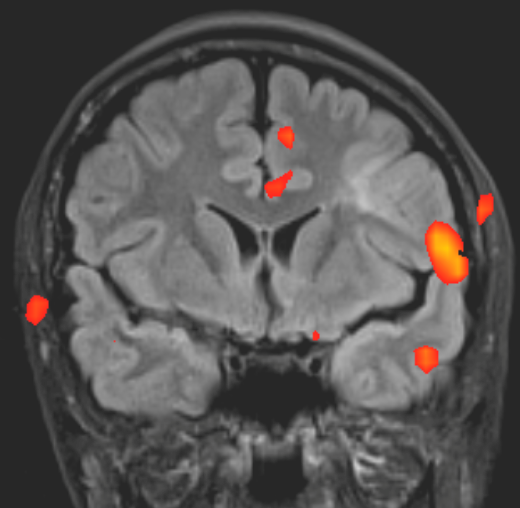

Tranzitorna (prolazna) globalna amnezija

Vrijeme čitanja članka: 2 minuteTranzitorna globalna amnezija je iznenadna, kratkotrajna epizoda gubitka memorije. Iako se smatra da je puno rjeđa od moždanog udara, bolesnici s takvom kliničkom slikom često se javljaju u hitnu neurološku ambulantu.